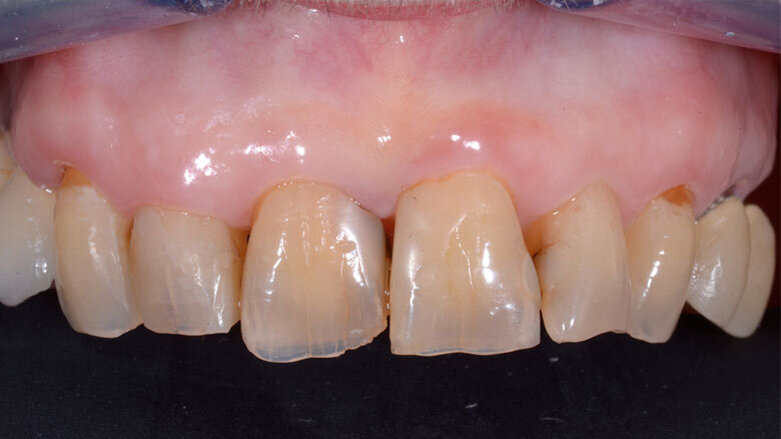

Un moncone in titanio per protesizzazione provvisoria (componente secondaria provvisoria - Straumann) viene modificato così da permettere un corretto alloggiamento della corona provvisoria e serrato manualmente. Protetto il canale della vite, il provvisorio viene forato in corrispondenza dell’accesso della vite protesica, posizionato in sede grazie alle alette e bloccato utilizzando del composito flow (G-aenial Universal flo - GC). Rimossa dal cavo orale, la corona provvisoria viene rifinita in laboratorio, completando il tragitto transmucoso in composito (Essentia Universal - GC) in modo tale da modellare un’area sotto-gengivale che sostenga i tessuti senza comprimerli. La riabilitazione provvisoria viene posizionata, avvitata e serrata a 20 N/cm. Il foro di accesso viene protetto con PTFE e sigillato con un’otturazione provvisoria (Telio CS onlay - Ivoclar), e i contatti occlusali vengono scaricati in modo tale da eliminare interferenze occlusali (Figg. 5, 6). Viene prescritta terapia farmacologica antibiotica, antidolorifica e sciacqui con collutorio a base di clorexidina digluconato. La paziente viene controllata a 7 giorni, 45 giorni e 90 giorni. A distanza di 3 mesi l’impianto viene considerato osteointegrato e i tessuti molli hanno raggiunto la loro stabilità. Il provvisorio viene quindi svitato (Fig. 7) e si procede tramite impronta ottica (Trios 3 - 3Shape) al trasferimento in laboratorio della posizione tridimensionale dell’impianto, della morfologia del tragitto transmucoso e della morfologia della componente sottogengivale della corona provvisoria (Figg. 8a, 9b). Una corona avvitata in zirconia con microstratificazione vestibolare viene confezionata come riabilitazione definitiva (Fig. 10). Superata la prova estetica, il manufatto viene consegnato e serrato a 35 N/cm. Il foro passante viene sigillato con PTFE e resina composita (G-aenial - GC) (Figg. 11, 12).

Fig. 5 - Valutazione post-operatoria con il provvisorio in situ - visione frontale.